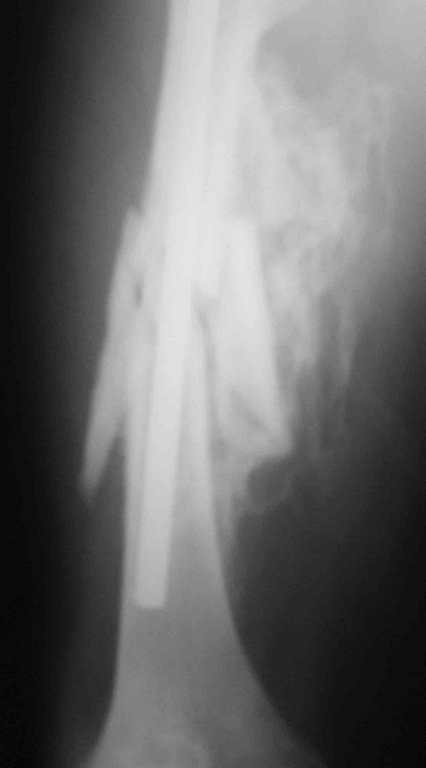

Re: 32- летний пациент с переломами обоих бедер после неудачного оперативного и консервативного лечения.

Иллюстрации к сообщению

Cyдя по представленным рентгенограммам оба бедра консолидированы. Необходима активная разработка движений в коленных суставах. Хотелось бы увидеть фотоснимки больного ( нижних конечностей спереди и сбоку). Если стержень мешает разработке движений то его надо удалить.

О происхождении такого запущенного случая- мой коллега работает экспертом ВТЭК и тянет в отделении и не такие казусы. Сегодня была сделана операция удален стержень из бедра и установлен стержневой аппарат из 2 опор, слева подвижности не наблюдалось, продолжается ЛФК. При необходимости позднее будет выполнена надмыщелковая корригирующая остеотомия. Спасибо всем за советы.